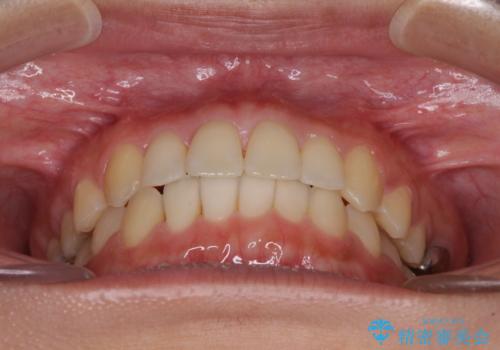

治療期間が世界的な感染症の流行時期と重なったため、海外と日本での往来が困難となり、治療継続が懸念されました。

それでも、しっかりとマウスピースを装着してくださったので、大きなトラブルもなく治療を終えることができました。